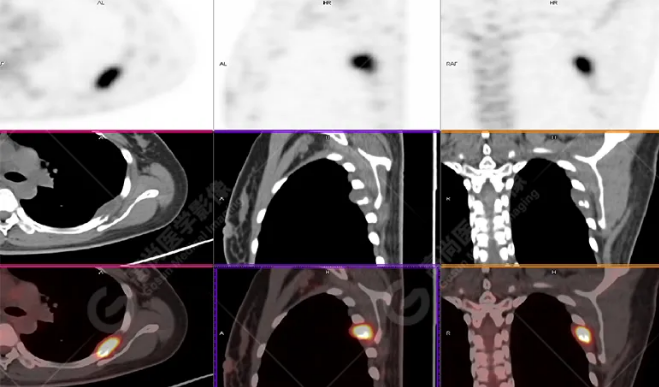

病史摘要:女性 36歲 因左后肋區(qū)疼痛1月余查體,無其他不適。PET/CT影像圖

左胸一后肋溶骨性骨質(zhì)破壞,周圍伴軟組織形成,F(xiàn)DG代謝增高,SUVmax為10.9。

找到引起骨痛病灶,病因:原發(fā)?轉(zhuǎn)移?感染?

最終診斷:宮頸癌伴肋骨單發(fā)骨轉(zhuǎn)移。